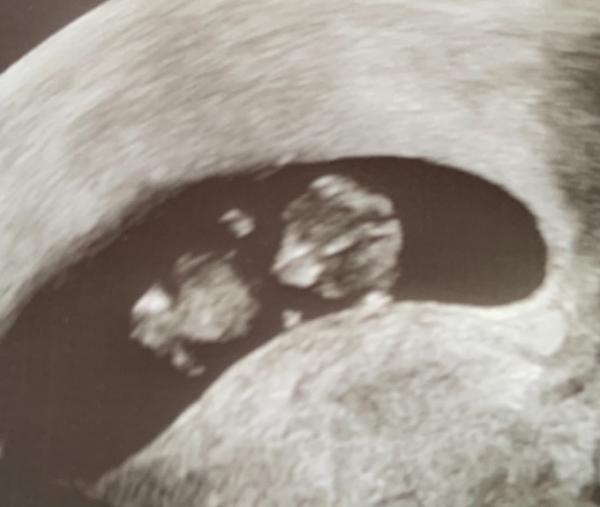

Heute war auch mein Termin und alles ist super entwickelt. Sie hat sogar die Nackenfalte gemessen und geschaut, ob der Rücken und Bauch geschlossen ist usw. sie sagt ist alles super da ich ja unsicher wegen den ganzen Tests war und sie nichts auffälliges entdeckt hat lassen wir es nun dabei. Ich freue mich sehr, dass ich mich nun entschieden habe einfach nichts mehr zu machen und daran zu glauben, dass mein Gummibärchen gesund ist Nackenfalte war toll und nächstes Mal schaut sie nach der Nase sagt sie aber so wie es nun ist, wäre es perfekt sie meinte, wenn wir sowieso das Kleine bekommen wollen dann würde das ausreichen. Zu viel verrückt machen ist auch nichts.. jedenfalls bei mir nicht.. mach mich eh immer kirre alles liebe an alle

Aber Moment mal: da fehlt doch ein Hals? Kleiner Spaß Schön, dass alles in Ordnung ist. In zwei Tagen bewältigen wir hoffentlich die Hürde Herzschlag. Mach dich nicht so kirre.

Haha ja stimmt, sieht aus wie ohne Hals danke auf dem anderen Bild wo ich hab sieht man ihn zum Glück haha es lag so super, schade das es für das Geschlecht noch zu früh ist.. Oh ja der Herzschlag ist ein toller Meilenstein

Oh wie schön, sehr süsses Bild So langsam werden tatsächlich kleine Menschen erkennbar Freut mich, dass alles gut ist! Darf ich fragen, wie groß euer Krümel jetzt schon ist? Weiterhin alles Gute Claudi

Hallo Claudi Danke, ja die Kinder erkennen endlich ihr Geschwisterchen das ist so toll ich finde auch, dass man so irgendwie noch mehr Bezug bekommt, wenn man schon ein kleines Baby mit Armen und Beinen usw. entdeckt sie sagte es sei so ca 3 cm groß, genau habe ich leider keine Maße. Sie sagte sei aber genau richtig für Anfang 11. Woche. Gute Frage, wie es bei den anderen ist. Wüsste ich auch gerne